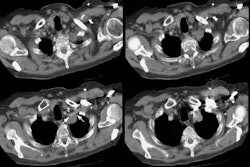

Example of the normal hilar interstitium: The images below are from a patient without bronchogenic carcinoma. The images demonstrate normal hilar lymphatic tissue (yellow arrow right image) which appears as a low density region between the bronchus and pulmonary vessel. A small calcified node is seen on the right (red arrow) in this patient with prior granulomatous disease. NOTE: Click image to enlarge.